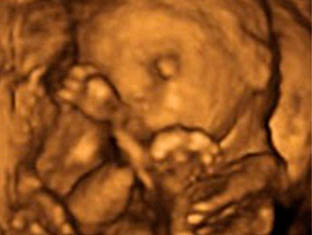

El embrión mide entre 2 y 3 centímetros en la semana 9 de embarazo y su forma ya es mucho más parecida a un ser humano: Aparecen las manos con los dedos y las muñecas, Las piernas se alargan aparecen los pies con sus dedos correspondientes. La cabeza sigue siendo la parte más grande en proporción con el resto del cuerpo los párpados cubren parcialmente los ojos. Los pabellones auriculares están bien formados. La boca se aprecia e incluso se abre.

La longitud del embrión es de 3 a 4 centímetros y su peso, unos 5 gramos. Podemos determinar el peso del embrión. El embrión cada vez tiene más forma humana y se distingue los brazos y los antebrazos, así como las manos que se abren y se cierran y están a la altura de la boca. La cara es más redondeada. Los ojos permanecen cerrados y la boca se abre y se cierra. La mineralización de los huesos progresa intensamente, sobre todo en el cráneo.